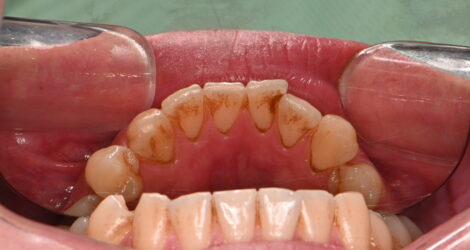

PMTC⑤

こんにちは。歯科衛生士の舘山です。

今回は着色をキレイに取って欲しい患者様にPMTCを行った症例を紹介したいと思います❗️

久しぶりの歯医者で着色が気になるとの事だったので60分の保険外クリーニングのPMTCをさせて頂きました。

術前↓